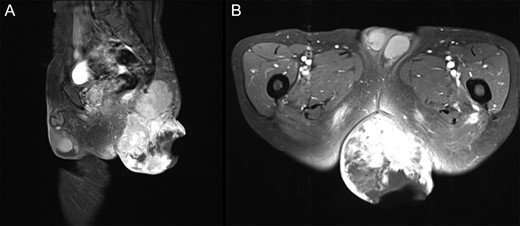

A 74-year-old male presented to our institution with soft tissue sarcoma in the left gluteal region and bleeding from the tumor (Fig. 1A). The perianal tumor was 15 cm in size. Redness, exudation and fetid odor were observed, and the patient exhibited poor mobility compared to baseline. Although the Eastern Cooperative Oncology Group Performance Status was 0 [2], the patient was unable to tolerate the supine position due to the giant tumor mass and also required assistance for defecation. On contrast-enhanced MRI, a tumor with fatty component was revealed primarily inside the left gluteus maximus muscle (Fig. 2A and B). On culture examination, Streptococcus gallolyticus, Bacteroides fragilis and Enterococcus avium were identified from the wound exudate, which was suggestive of an infection concurrent with the tumor. The needle biopsy indicated a spindle cell tumor with positive immunostaining for MDM2 and Cdk4. Based on these findings, the left gluteal region was diagnosed as dedifferentiated liposarcoma with wound infection and American Joint Committee on Cancer Stage III (T2bN0M0, high grade).

T1WI contrast-enhanced MRI with fat suppression at first visit. (A) Sagittal image. (B) Axial image. Left gluteal region: a 15 cm tumor extending from the gluteus maximus muscle to the subcutaneous tissue with enhancement of irregular margins was observed. A portion of the tumor had disintegrated, and the internal mass was heterogeneous.